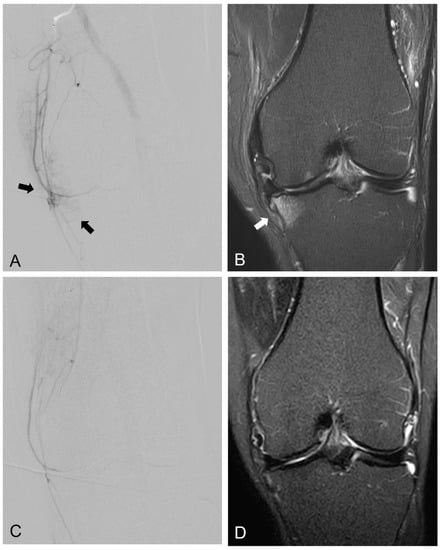

- Okuno, Y.; Korchi, A.M.; Shinjo, T.; Kato, S.; Kaneko, T. Midterm Clinical Outcomes and MR Imaging Changes after Transcatheter Arterial Embolization as a Treatment for Mild to Moderate Radiographic Knee Osteoarthritis Resistant to Conservative Treatment. J. Vasc. Interv. Radiol. 2017, 28, 995–1002. [Google Scholar] [CrossRef]

- Choi, J.W.; Ro, D.H.; Chae, H.D.; Kim, D.H.; Lee, M.; Hur, S.; Kim, H.C.; Jae, H.J.; Chung, J.W. The Value of Preprocedural MR Imaging in Genicular Artery Embolization for Patients with Osteoarthritic Knee Pain. J. Vasc. Interv. Radiol. 2020, 31, 2043–2050. [Google Scholar] [CrossRef]

- Wang, B.; Tai, T.-W.; Liang, K.-W.; Wang, C.-K.; Liu, Y.-S.; Huang, M.-T.; Chang, C.-W. Short-term effects of genicular artery embolization on bone marrow lesions in patients with refractory knee osteoarthritis. 2022; unpublished. [Google Scholar]